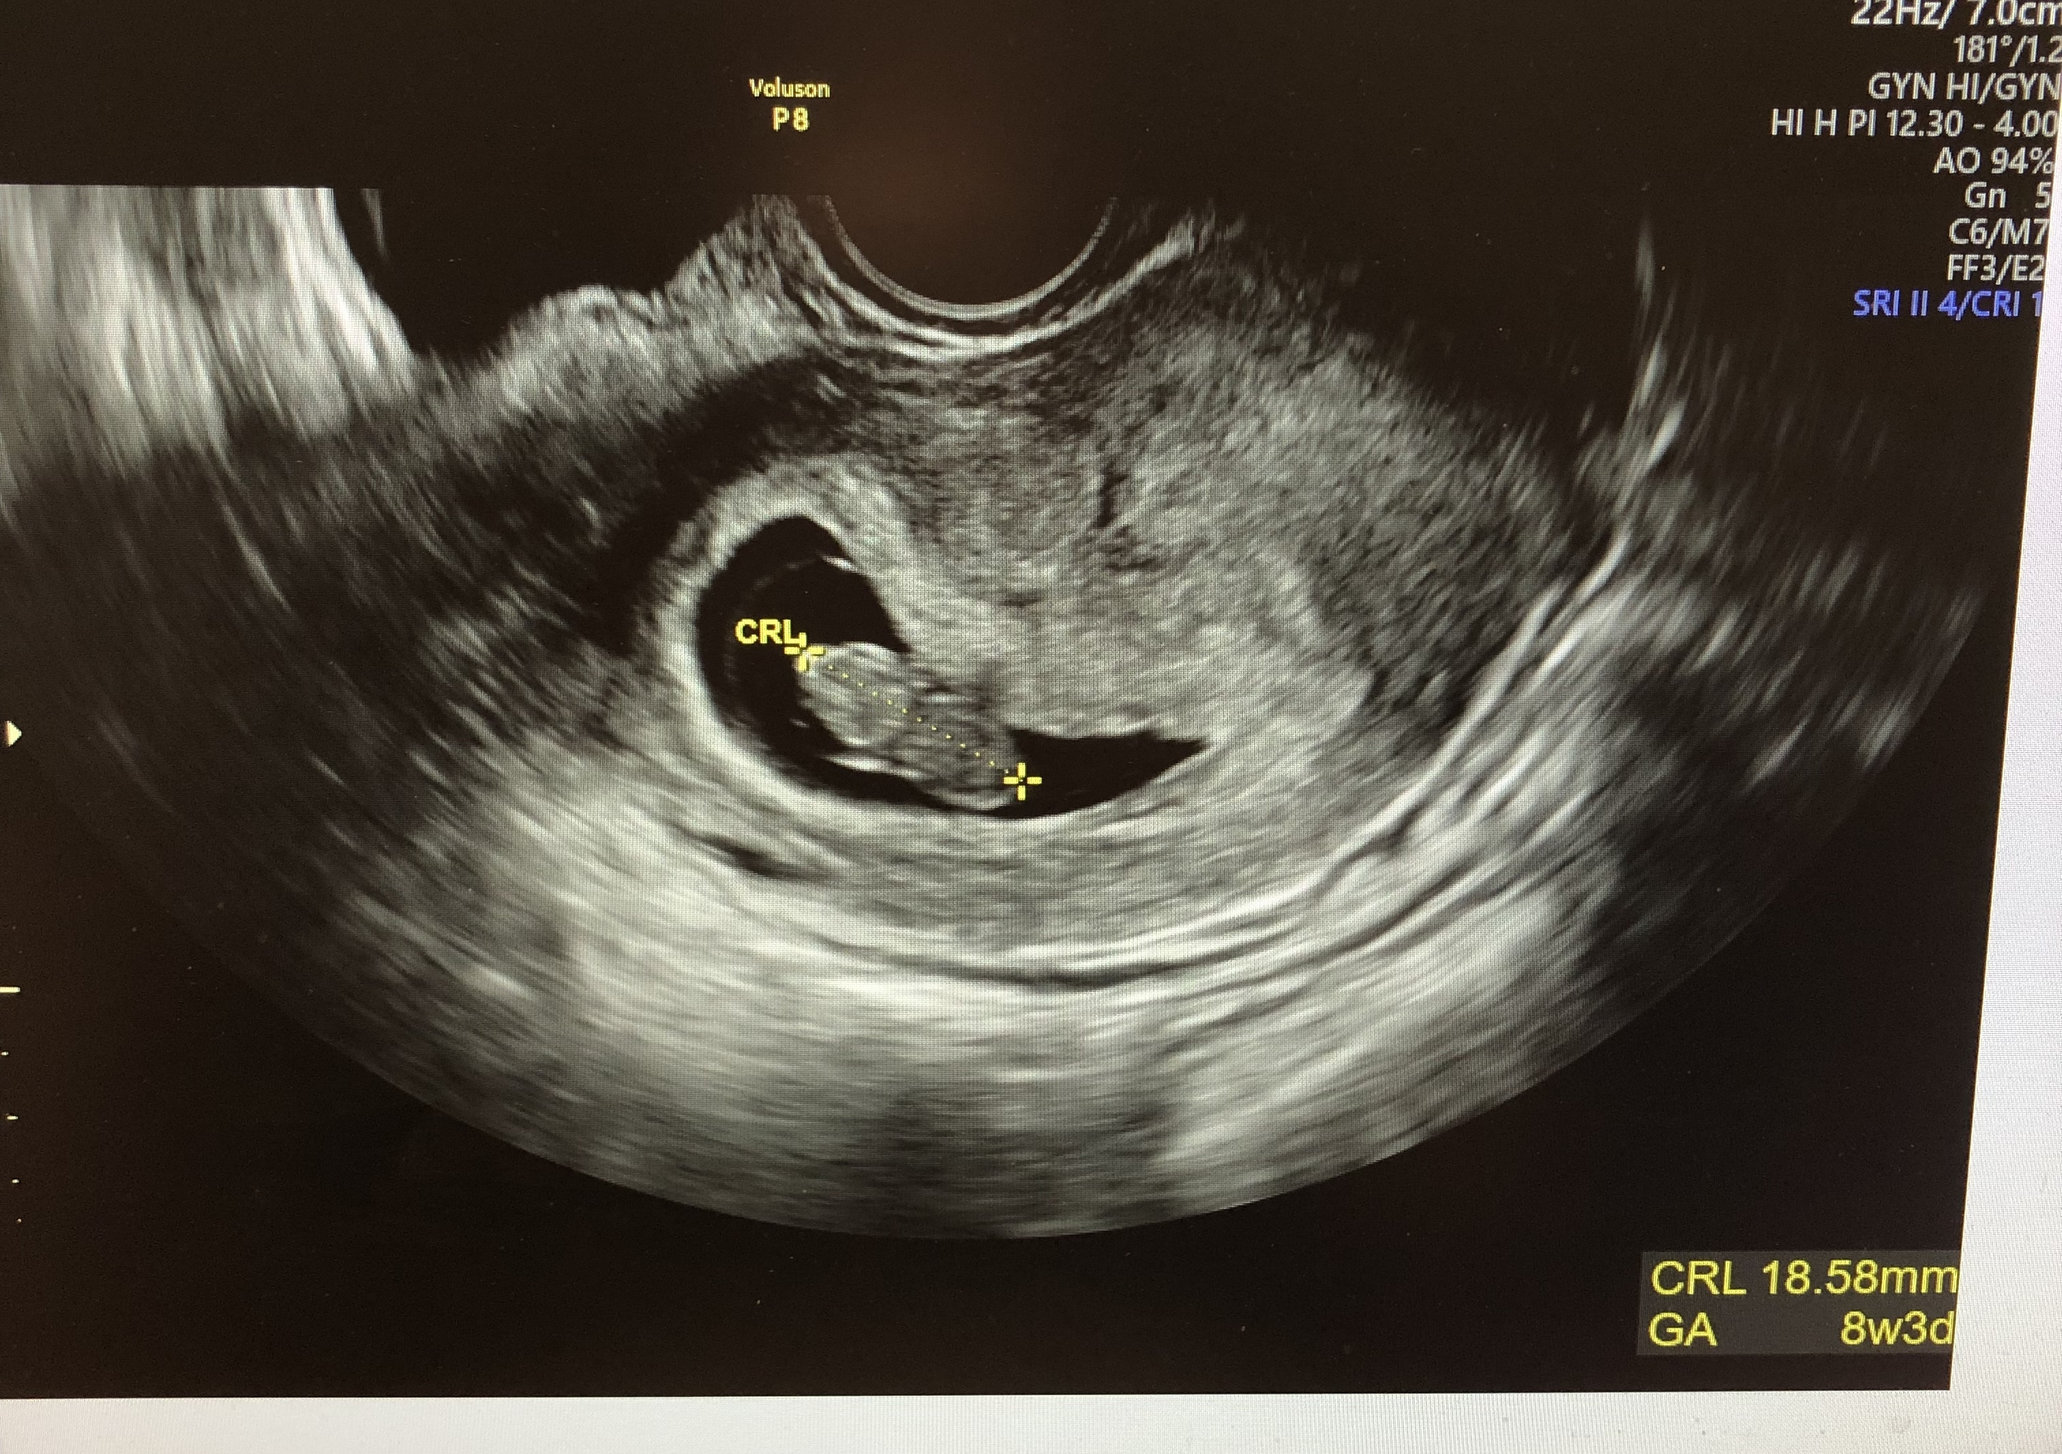

Jan 19 2018 - Fresh Transfer #1 one 5dt; BFP 1/25/2018; EDD 10/7/2018; MMC at 8w3d; D&C 3/6/2018

Well No more PIO for this girl!!! Graduated from my RE today 😊 little man is looking great! Next stop OB on 12/18!

I just had my first OB appointment today--definitely a different experience. Took vitals, 6 vials of blood, and urine. Then i had an U/S but i didn't get print out!? Maybe i should have asked for a copy--but it seems like it would be a no brainer. I didn't push it b/c the images weren't as nice as the ones i had from the RE but still. HR was 171 so that was nice to know.